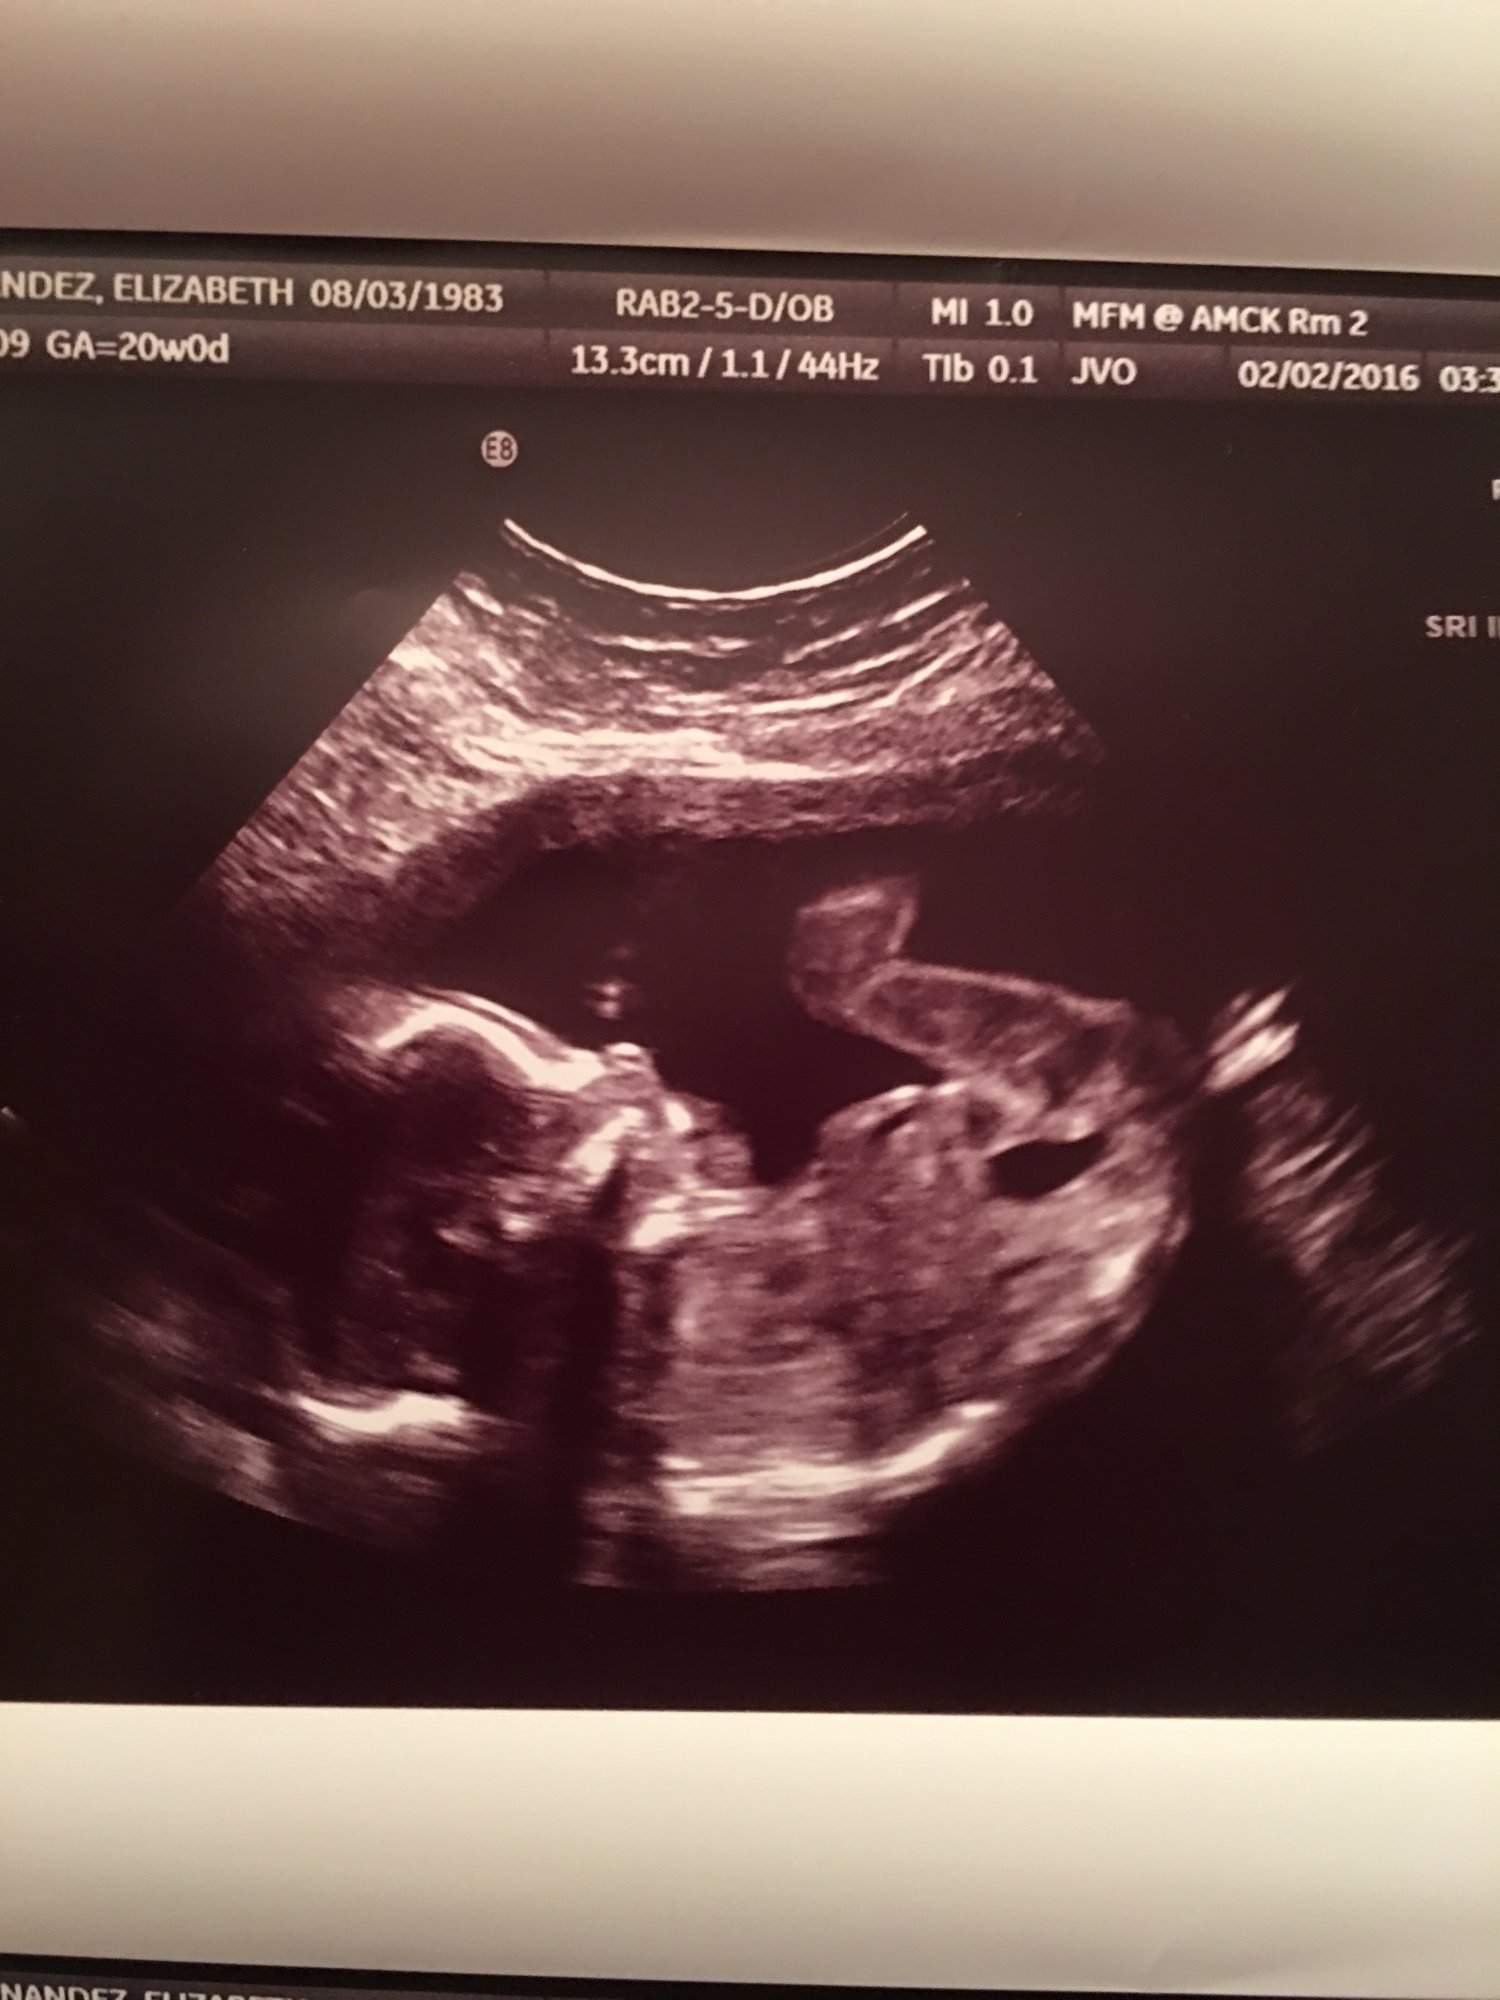

My baby girl.. Getting ready to kick me at our 20 week scan with the perinatologist.